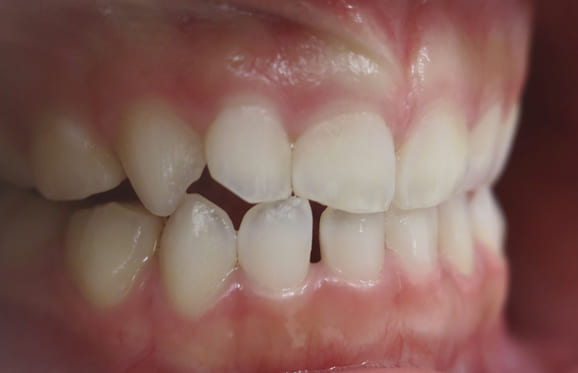

● 歯根が折れ保存不可の歯を抜歯して、そのスペースに八重歯を並べた症例

藤沢デンタルオフィスの虫歯や破折で抜歯後の部分矯正